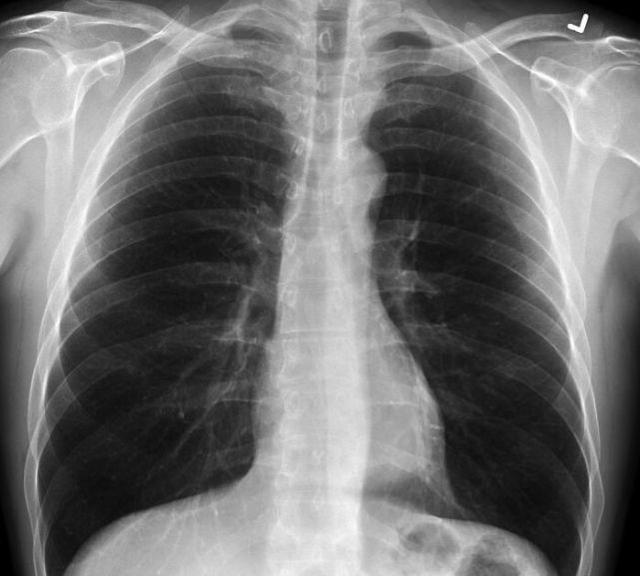

医生发布了三张肺部X光的照片,其中一名健康患者,一名吸烟者和一名COVID-19患者,以指出差异。

不吸烟人的肺部很干净,它们有很多黑色空间,这表明一个人可以吸入大量空气